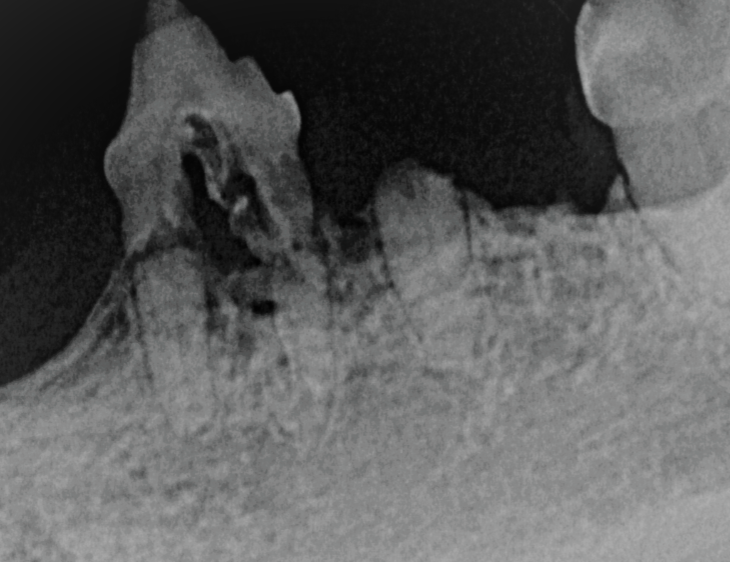

Photo 3 - abgebauter Knochen

Photo 5 - abgebauter KnochenPhoto 4 - abgebauter Knochen

Auf den 3 Bildern sieht man jeweils wie der Knochen sich aufgrund einer Entzündung abgebaut hat.

Werden die Zähne geröntgt, können wir sehen was genau mit dem Knochen durch die Entzündung passiert ist und welcher Zahn gezogen werden muss. Ohne Röntgen sieht man nur die Spitze des Eisberges.